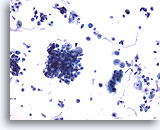

Figure 2

Bronchoalveolar lavage

Both macrophages and bronchial epithelial cells may be multinucleated. 40x

Bronchoalveolar lavage

Both macrophages and bronchial epithelial cells may be multinucleated. 40x

Figure 2

Bronchoalveolar lavage

Both macrophages and bronchial epithelial cells may be multinucleated.

40x

Bronchoalveolar lavage

Both macrophages and bronchial epithelial cells may be multinucleated.

40x